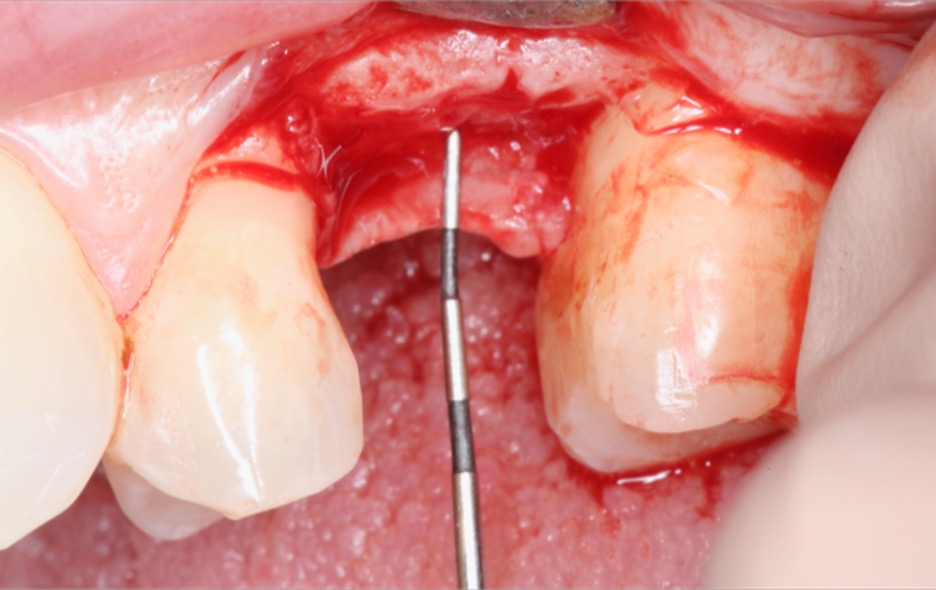

More recently, the depth of the implant has been described as a position of the IPD relative to the soft tissue9 (Figure 5). Linkevičius reported that vertical soft tissue is a key determinant of crestal bone maintenance.9 In the immediate placement of implants, it is important to note that tissues are usually scalloped; thus, the vertical tissue depth requires further description.

Fig 3. The vertical soft tissue is measured from the IPD to the crestal soft-tissue zenith.

Figure 3